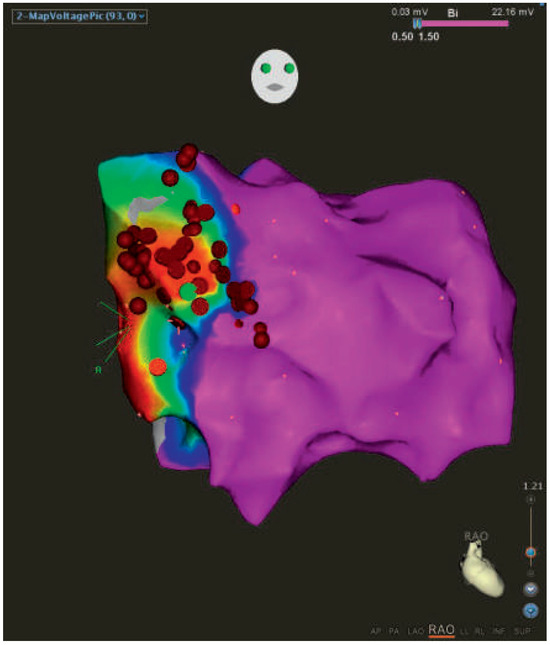

Topsy-Turvy Ventricular Tachycardia

by Federico Moccetti, Jan Novak, Aline Mühl and Michael Kühne

Cardiovasc. Med. 2016, 19(4), 132; https://doi.org/10.4414/cvm.2016.00409 - 20 Apr 2016

We present the case of a 72-year-old male with a history of coronary artery disease and an inferior myocardial infarction 19 years previously, when the occluded right coronary artery was percutaneously revascularised [...] Full article